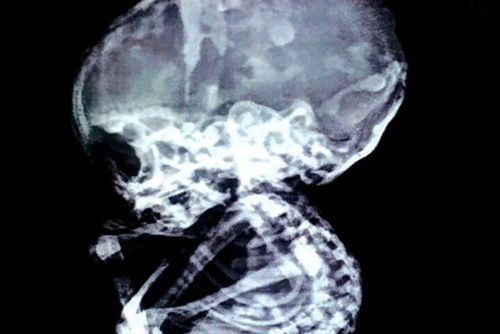

Một chuyên gia sản khoa đã vô cùng bất ngờ khi phát hiện một bào thai hoá đái trong bụng người mẹ hơn 15 năm.

Do gia đình chồng không chấp nhận đứa trẻ nên đường cùng người phụ nữ ở Ấn Độ đã phải phá thai. Thế nhưng 15 năm sau, các bác sĩ bàng hoàng phát hiện thai nhi vẫn nằm trong bụng mẹ.

Thai nhi hóa đá 44 năm trong bụng bà lão được ra đời...